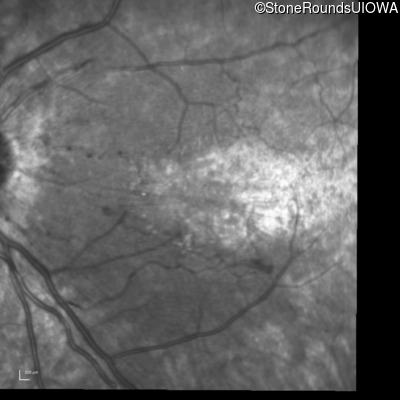

Infrared Fundus Photograph - Left - 20/80 -1

Exemplar